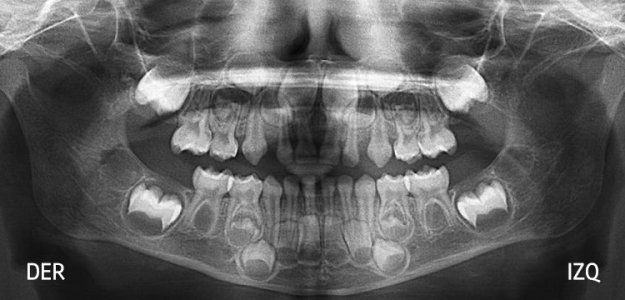

Panorámica